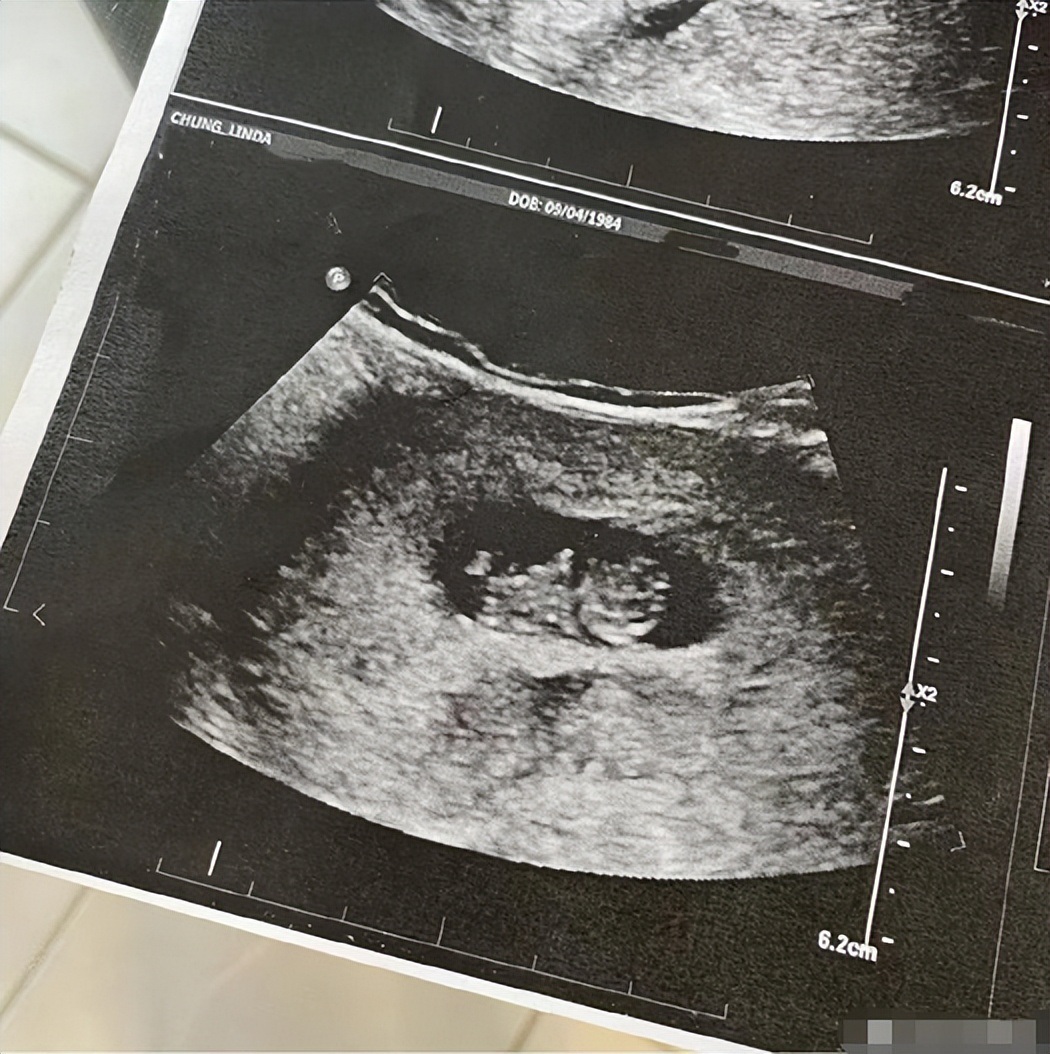

更是直接在社交平台晒出自己的B超照片,从照片中看到虽然宝宝不是很大,但是还是清晰可见的外形。看样子,钟嘉欣一家十分欢喜这个孩子的到来。